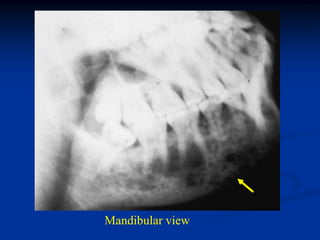

Case #435

4 year female

EG right mandible

Oral photo of submucosal mass

Mandibular view

Full mouth dental x-ray view

Axial CT scan

Photomic